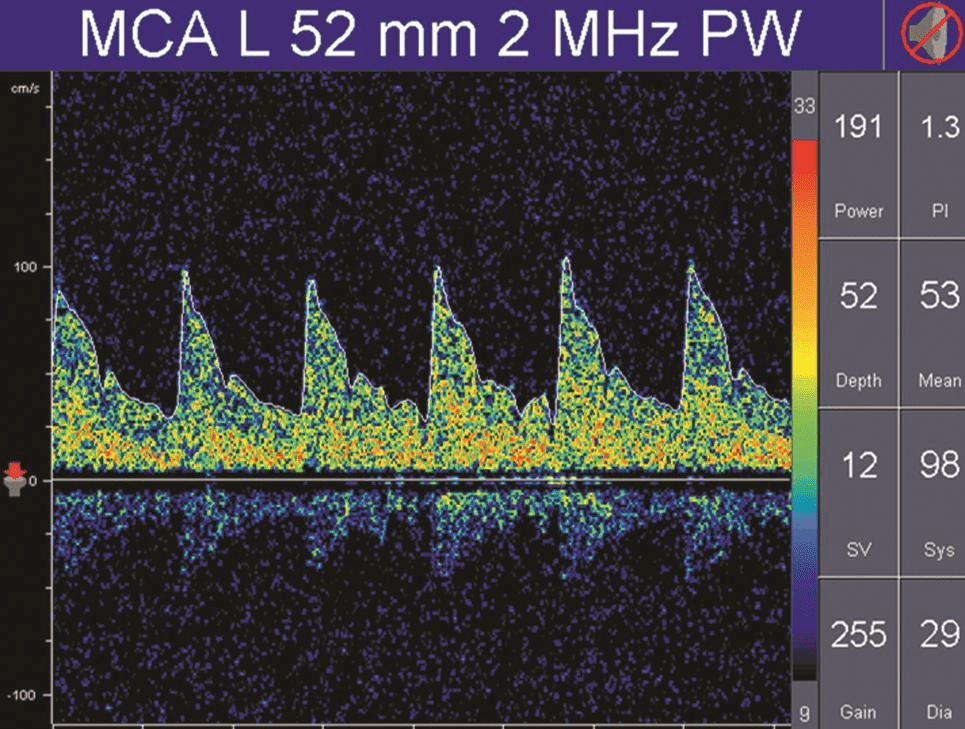

搏動指數(shù)(pulsatility index,PI)和阻力指數(shù)(resistant index,RI)是描述頻譜形態(tài)的參數(shù),通常是由血流速度計算出來,計算公式為:PI=(Vs-Vd) /Vm,RI=(Vs-Vd) /Vs。

PI值主要受收縮期和舒張期血流速度差的影響,差值越大,PI值越大;差值越小,PI值也越小。

因此,PI值可以反映血管內(nèi)血流壓力灌注情況或遠端血管的阻力大小。

正常情況下顱內(nèi)血管的血流頻譜為相對低搏動性波形(PI值為0.55~1.05),而外周血管(顱外頸動脈或肢體血管)為相對高搏動性或高阻力波形(PI值通常大于1.05),顱內(nèi)正常搏動指數(shù)和阻力指數(shù)的頻譜(詳情見下圖)。

而高阻力頻譜則見于顱內(nèi)壓增高、大動脈嚴重狹窄或閉塞的近端血管,以及長期高血壓受檢者(詳情見下圖)。

TCD多普勒高阻力血流頻譜

可見,除血流速度和血流方向之外,PI值是分析TCD血流頻譜的另一個非常重要的參數(shù)。